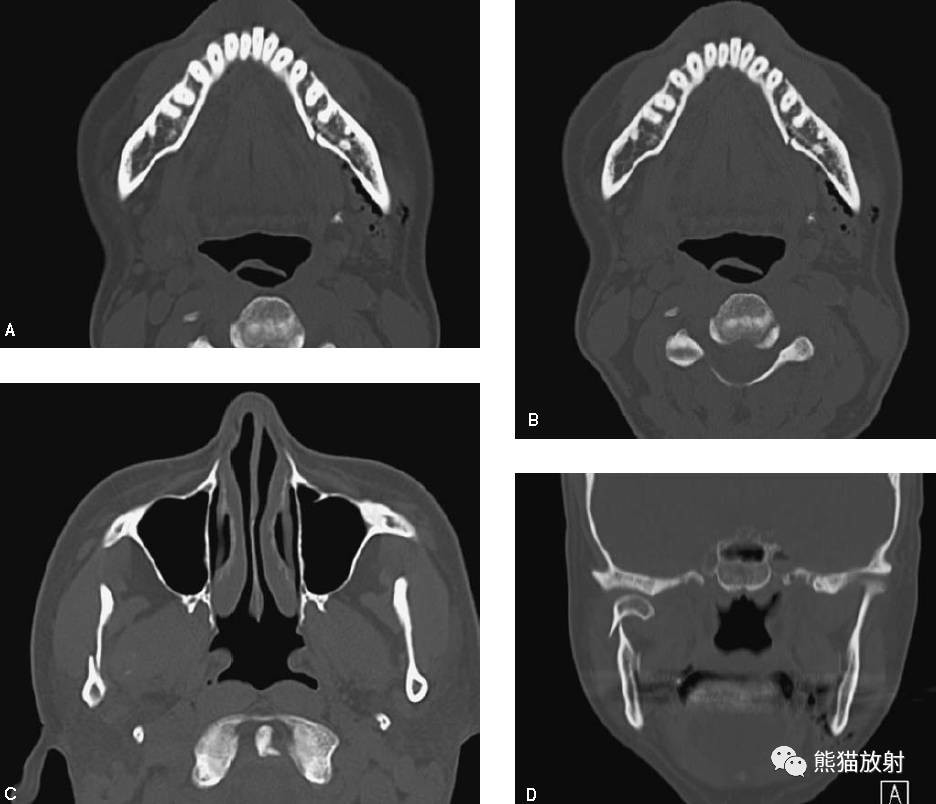

颞下颌关节ct

颞下颌关节紊乱ct 能否正畸呢?

颞下颌关节ct扫描重建效果 - 好大夫在线

【求助】颞骨ct平扫

颞骨ct 水平位